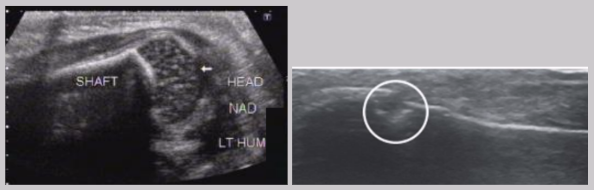

Achilles tendon

Strongest and thickest tendon in the body

Attachments

Proximal - gastrocnemius and soleus muscles

Distal - calcaneus (heel bone)

Normal US appearance of Achilles tendon

Common Achilles tendon pathology

Tendinopathy

Partial or complete tears

Retrocalcaneal bursitis

Partial or complete Achilles tendon tears